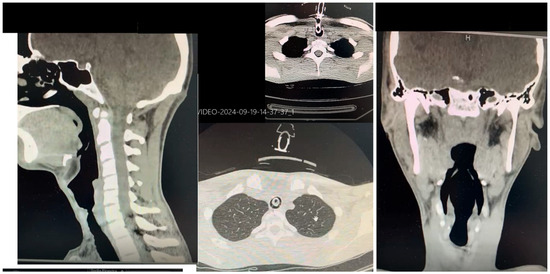

Another crucial aspect in evaluating surgical eligibility is the precise timing of the procedure. Inappropriate timing—such as in the presence of clinical instability or active respiratory infections—could severely compromise the surgical outcome. Equally fundamental are the diagnostic–functional assessments requested by the thoracic team. For surgical planning, the thoracic team required a series of targeted investigations to define both the fistula’s anatomical features and the patient’s overall condition. These included a computed tomography (CT) scan of the neck and chest (Figure 2), a dynamic video of the patient in full cervical extension (Figure 4), videolaryngoscopy (Figure 3), as well as assessments of nutritional, neurological, and general medical status.

The CT scan (Figure 2) allowed clear visualization of tracheal narrowing below the cricoid and identified indirect signs of TEF, providing critical preoperative information (Figure 2). The dynamic video in maximal cervical extension is especially useful in patients with potential post-coma rigidity or dystonia, allowing the surgical team to pre-empt challenges in field exposure, especially with anterior tracheal approaches (Figure 4). Nutritional assessment included confirming the correct positioning of the PEG, which is essential to ensure appropriate nutritional support both before and after the operation. Lastly, neurological and general clinical evaluations were required to exclude haemodynamic instability, ongoing airway infections, or other contraindications to major thoracic surgery. Even partial neurological cooperation was considered a favourable factor.

Figure 4. Photographic documentation of preoperative dynamic assessment of the cervical spine, performed with an armored size 8 tracheostomy cannula in situ. This evaluation, conducted to assess cervical mobility and surgical accessibility in maximum extension, is an essential component of the preoperative protocol. Together with CT imaging of the neck and chest and clinical–nutritional stability, it supports surgical planning for tracheoesophageal fistula repair in coordination with the thoracic surgery team.